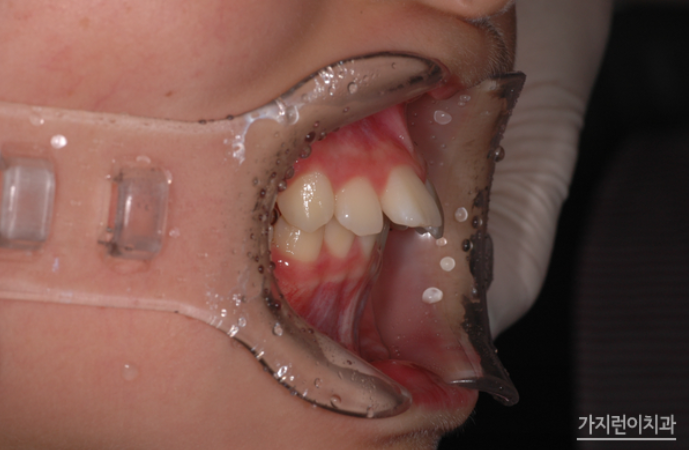

위 환자분의 경우 위턱의 과성장과 아래턱의 저성장이 동반된 사례였인데요. 대문니의 경우에는 기울어진 각도 때문에 대칭을 이룬 이의 크기가 달라 보이기도 하는데 자연치아를 살리는 것이 가장 좋은 방법이기 때문에 비발치로 치아교정을 진행해봤습니다.

교정용 헤드기어와 스크류를 적극 활용한 케이스라고 할 수 있는데요. 헤드기어의 경우 통상적으로 하루에 12시간 이상 착용을 해야 하기 때문에 주로 취침 시 착용할 것을 권고하는데요. 임의대로 시간을 조절해 착용해서는 안 됩니다. 제대로 시간을 지키지 않을 시 어금니가 이동하지 않아 충분한 공간 확보가 어려워져 결국 발치가 할 수도 있는데요. 때문에 치아의 이동양상에 따라 치과를 방문해 팽팽함을 유지해야 합니다. 여기에 뻐드러진 앞니가 제자리를 찾을 수 있도록 미니스크류를 식립하여 위턱 전체 치열을 후방으로 이동시켰는데요.